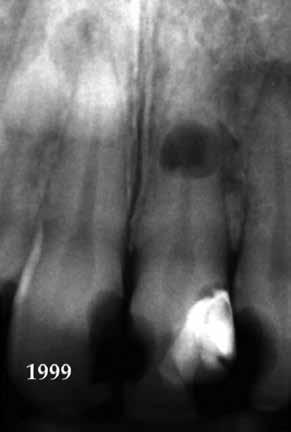

10. ábra: A periapikális felvételen egyértelműen megmutatkozik a 46-os és 47-es fogak között kialakult csontos defektus, valamint a gyökereket fedő parodontális rostok károsodása. – 11. ábra: A disztális gyökér amputációját követően a csonthiány kiterjedése látszólag tovább növekedett. – 12. ábra: A 22 évvel később készített kontrollfelvételen jól megfigyelhető a csontos defektus telődése, valamint új kortikális csontállomány kialakulása.

Gyökéramputációt főként a furkáció érintett nagyőrlő fogak ellátása során szoktunk alkalmazni. Derks és mtsai. vizsgálatában a gyökéramputált nagyőrlő fogak közel 80%-a 20 évvel a beavatkozás elvégzését követően is megtartott volt. 1998 októberében egy 39 éves férfi páciens a jobb alsó kvadránsban jelentkező ínyérzékenység miatt kereste fel rendelőnket. A klinikai vizsgálat során jobb alsó első és második nagyőrlő fog között (46–47) nagy kiterjedésű csontveszteséget észleltünk. Ettől eltekintve a teljes fogazat parodontális státusza megfelelőnek bizonyult. A jobb alsó kvadránsban végzett szenzibilitás vizsgálat során arra az eredménye jutottunk, hogy a 46-os fog vélelmezhetően elhalt (10. ábra).

A páciens beleegyezését követően a 46-os fog disztális gyökere, a disztális gyökér felett lévő koronális rész megőrzése mellett rezekcióra került (11. ábra). A rezekciót követően a referáló orvos a 46. és 47. fogak koronáját Ribbond szalag és kompozit segítségével egymáshoz rögzítette. A sebészi beavatkozást követően 22 évvel készült kontrollfelvételen a lézió csontos telődése, kortikális csontállomány kialakulása, valamint a furkáció körüli csontos regeneráció volt megfigyelhető (12. ábra) A károsodott fogak megtartására szolgáló lehetőségek fejlődésének, valamint az implantátumok behelyezésével kapcsolatos rizikófaktorok jobb megértésének köszönhetően ma már más szemmel vizsgáljuk a fogak eltávolításának szükségességét. A kérdéses prognózissal vagy a kis protetikai értékkel rendelkező fogak eltávolítása előtt mindig érdemes felmérni az ezzel elérhető lehetséges előnyök nagyságát. A kemény- és lágyszöveti pótlás lehetőségeinek fejlődésével, a PRF elérhetőségével, a minimálinvazív sebészeti módszerek és az operációs mikroszkópok elterjedésével, valamint a varróanyagok és varrat technikák egyre kifinomultabbá válásával ma már alaposan el kell gondolkodnunk az előtt, hogy egy fogat egy implantátum behelyezése érdekében eltávolítsunk. Mára sokkal kedvezőbb prognózist és sokkal nagyobb sikerességet tudunk elérni a korábban menthetetlennek gondolt fogak kezelése során.